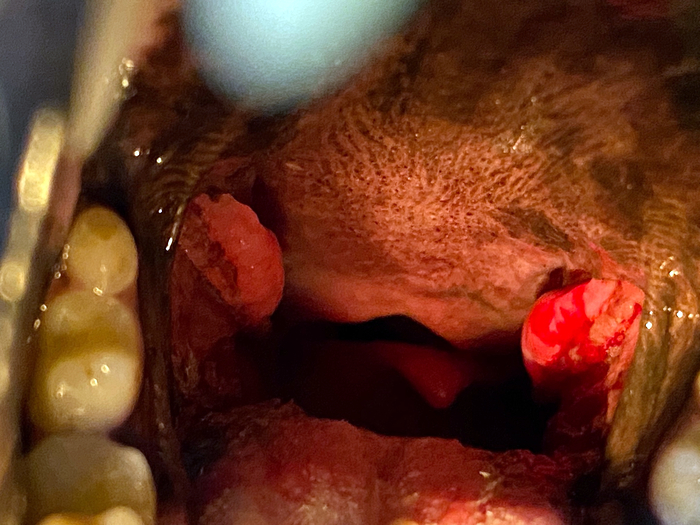

◆ 편도선염과 부종

양쪽 편도선이 부어있는 것 같았어요 특히 왼쪽 편도선은 출혈까지 확인되었는데

개가 콧물과 코 막힘의 증상과 킁킁 소리를 내며 내시경으로 후두부를 검사했습니다. 검사 결과 편도선 염증이 확인되었습니다.

편도선염 치료 후에 이 아이는 편도선염 치료를 실시했다고 합니다. 오랫동안 불편한 증상으로 지내온 아이는 이번 내시경 검사를 통해 편도선에 염증과 출혈이 있음을 확인하고 그에 맞는 치료를 할 수 있었습니다. 약물 복용을 장기간 했지만 완치되어 이후에는 비슷한 증상이 나타나지 않는다고 합니다.